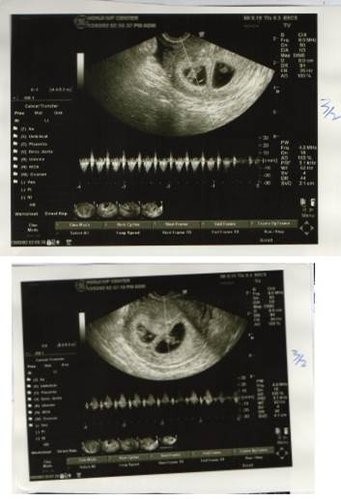

傳統試管嘗試2次沒成功,宏孕溫和刺激讓我順利懷了雙胞胎!今天3/15,滿9周了!

在宏孕診所第一次我只取到二顆卵,置放5天,一顆為囊胚A級,一顆為B級,玻璃冷凍後,進行第二次療程,這次取到3顆卵,2顆空包蛋,另1顆的品質似乎不如上次的2顆。因此,我決定植入上次的2顆,很順利的2顆胚胎都順利著床,也都有心跳。

現在,我跟我們的雙胞胎們一起畢業了!